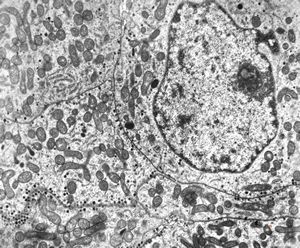

F,8y. | metachromatic leukodystrophy - n.suralis

F,25y. | metachromatic leukodystrophy - n.suralis

F,8y. | metachromatic leukodystrophy - n.suralis

F,25y. | metachromatic leukodystrophy - n.suralis

F,25y. | metachromatic leukodystrophy - n.suralis